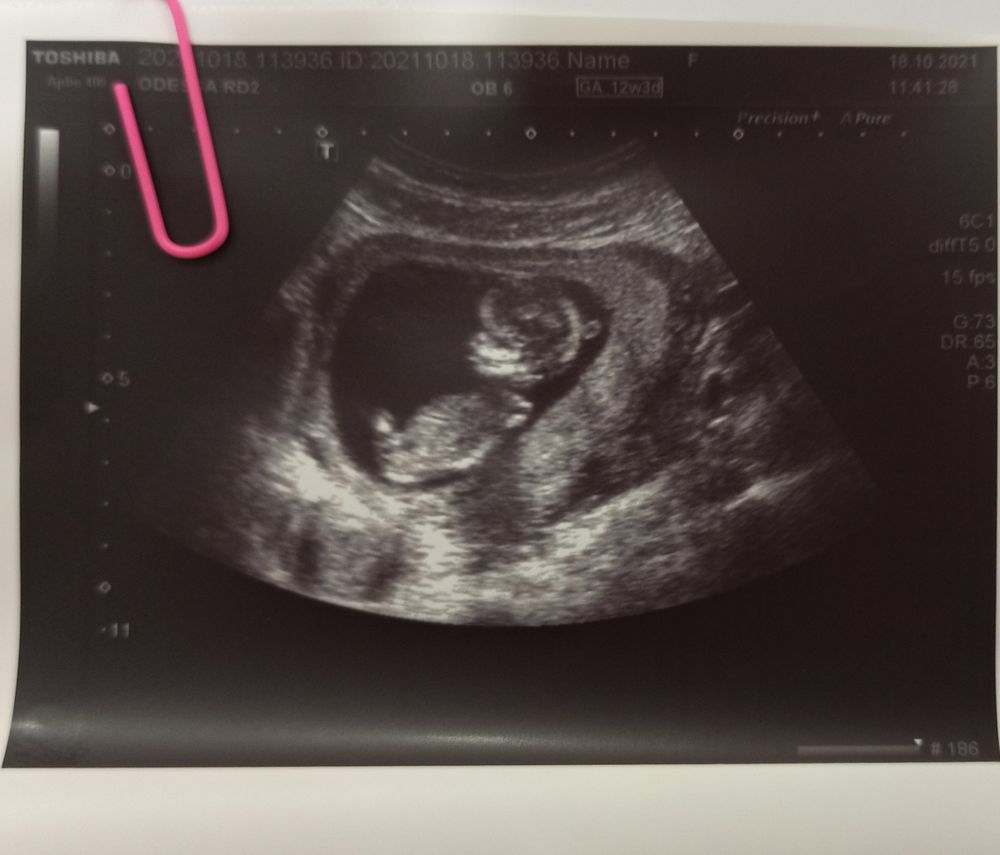

1 скрининг пройден🎉🥳

Первый скрининг самый страшный) у нас опережение на 1.5 недельки идёт (а ставят на 2, т.к. не могут делить). Растите, развивайтесь 🤗

Ириша, поздравлю вас с мужем 😍🤗🤗🤗. Какой хорошенький , малышок 👶🏻 🤗☺️. Значит быть нам мамами парнишек😃. Пусть растёт и развивается ваш малыш. Безумно рада, что у вас с малышом все хорошо. Отличное узи- это 99% процентов, что и кровь отличная! Выдыхай и расслабляйся, все страшное уже позади 🌸🌸🌸

у меня тоже в 12 недель плясал прям на узи , а в конце вообще попой повернулся

Анна , а мы в конце пяточку выставили 😁